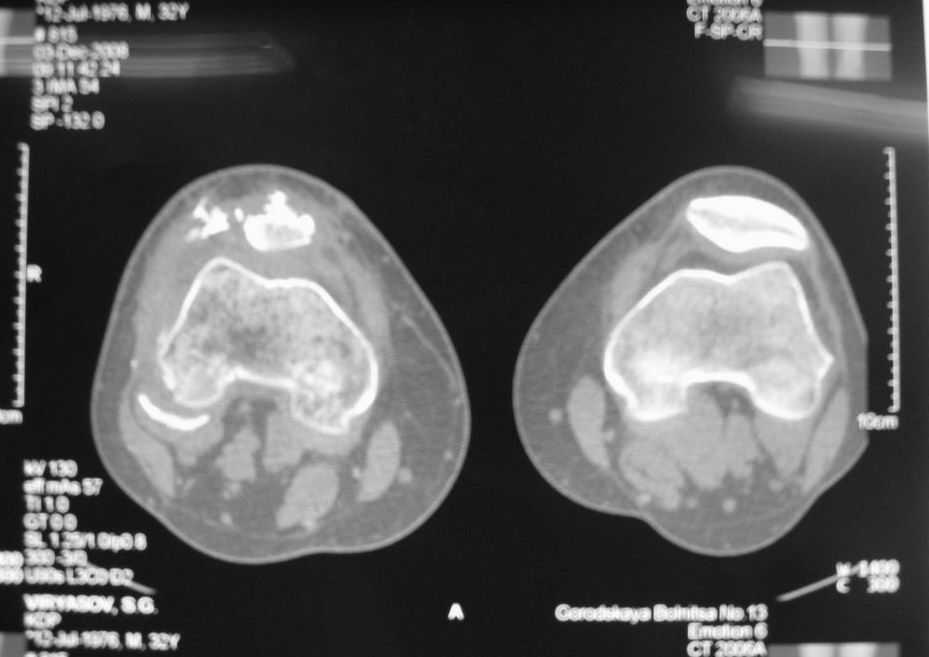

Уважаемые коллеги! Обратился пациент 32 лет с травмой коленного сустава от июля 2008 года - падение с мотоцикла, прямой удар передней поверхностью коленного сустава. Диагноз - открытый оскольчатый перелом надколенника. В одной из больниц города выполнили ПХО, шов надколенника лавсаном. Заживление раны с частичным нагноением(разведена на участке 3 см).

Сейчас мягкие ткани в порядке. R-снимки, КТ в приложении. Объем движений 0/0/110 гр.Ходит почти без хромоты.

Жалобы на торчащий под кожей один из отломков, боль в этой точке.Вопрос: что делать? Первое - убрать этот отломок и на этом закончить. Второе - оставить все как есть(отломок не так уж и сильно мешает). Ждать возможного развития артроза, дальше по ситуации. Третье - подумать о протезировании надколенника.